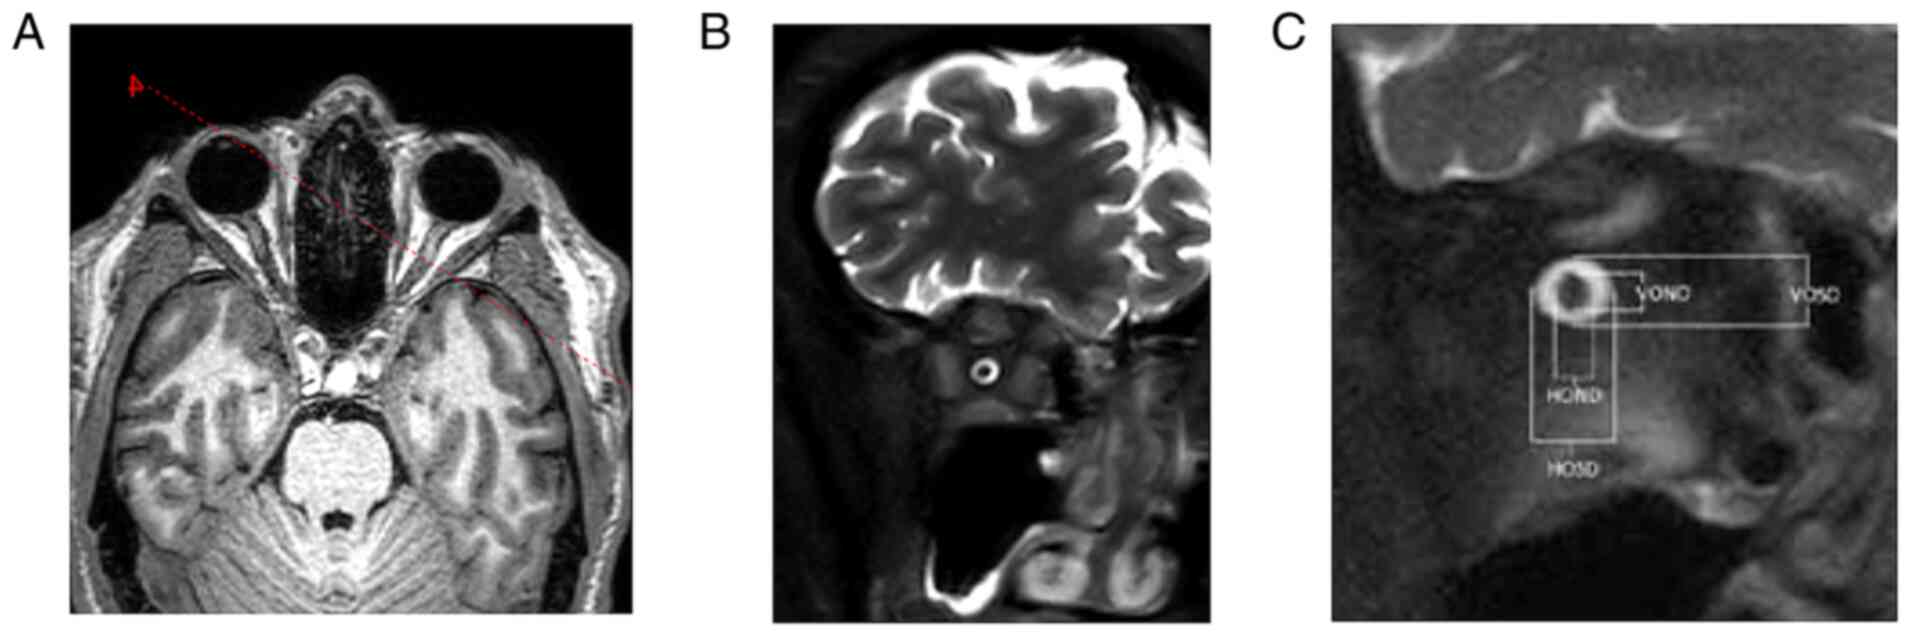

Structural MRI of the hypophysis and orbits was carried out on a 3T Achieva dStream TX SERIES (Philips HealthCare, Best) with a 32-channel SENSE RF head coil. The hypophysis was examined according to the protocol, with intravenous application of 10 ml of gadolinium contrast substance. MRI of the hypophysis employed a T1 TSE sagittal sequence, with 2-mm slice thickness, gap 0, TR 500, TE 10 native and after intravenous contrast substance application (Fig. 5). The targeted orbital examination employed an sT1 3D TFE sequence, with 1-mm-slice thickness, gap 0, TR 6.7, TE 3.1, primarily in the sagittal plane, T2 TSE mDIXON, 2.5-mm-slice thickness, gap 0.3, TR 3000, TE 80, in the coronal plane and targeted orbital sequences on both sides, T2 SPIR SSh, 3-mm-slice thickness, gap 0.3, TR 9520.2, TE 120.0. Optic nerve measurements were analyzed on IntelliSpace Portal working station version 10-1 (Philips Medical Systems). Coronal T2 SPIR SSh sequences were planned in the axial plane upright to the optical nerve in 4-8-16-20-mm intervals behind the dorsal eye contour for both sides. The measurement included the optic nerve's largest outer diameters in two perpendicular axes horizontally (ONDH) and vertically (ONDV), and optic nerve sheath diameters in two perpendicular axes horizontally (OSDH) and vertically (OSDV) in both previously mentioned intervals separately (Fig. 6 and Table I). The optic nerve chiasma was detected in the coronal plane in the T1 TFE 3D sequence at the point of its narrowest range, and the outer diameter in the horizontal plane was measured. The Parks et al algorithm was used to distinguish PA from craniopharyngioma (13).

Figure 6

(A) Magnetic resonance imaging sequence for the dimensional assessment of the optic nerve and its sheath (red planning line). (B) T1 Turbo Field Echo planning axial sequence for the coronal plane projecting vertically to the optic nerve and the right eye. (C) Coronal T2 Spectral Presaturation with Inversion Recovery Single Shot sequence for measurement of the right eye. HOSD, horizontal optic nerve sheath diameter; HOND, horizontal optic nerve diameter; VOSD, vertical optic nerve sheath diameter; VOND, vertical optic nerve diameter.

Table I

OND and OSD values at distances of 4, 8, 16 and 20 mm from the eyeball in the V and H plane.

Right eye, mmLeft eye, mm

Distance from eyeballONDOSDONDOSD

V43.06.82.86.7

H42.87.03.17.0

V82.96.33.16.3

H83.07.43.47.1

V162.55.02.24.4

H162.95.82.45.1

V202.85.42.45.6

H202.75.42.35.3

[i] OND, optic nerve diameter; OSD, optic nerve sheath diameter; V, vertical; H, horizontal.